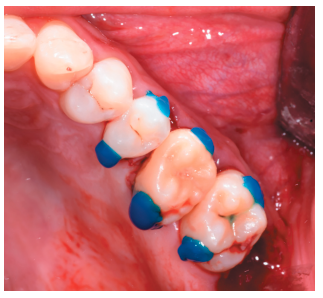

Caso clínico: se presenta el caso de un varón de 28 años, que acudió a consulta por la presencia de unos restos radiculares en localización de primer molar superior izquierdo. Se realizó un autotrasplante dental, siendo el diente donante el tercer molar superior izquierdo, que se trasplantó al alveolo del primer molar, mostrando buena evolución clínica y radiográfi ca.

Clinical case: a clinical case of a 28-yearold man is presented, who went to dental clinic for removal of left fi rst molar roots. An autotransplant was performed using left third molar as donor tooth, which was transplanted into fi rst molar alveolus, showing promising clinical and radiographic evolution.